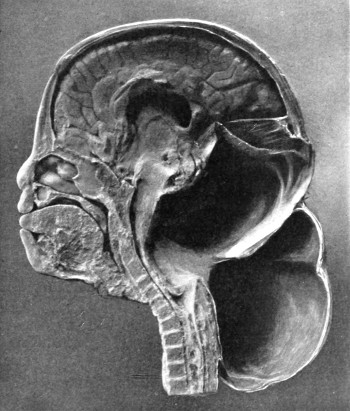

The child was 3 months old, and presented a tumour, the size of an orange, situated between the occipital protuberance and the nape of the neck. The mass was pedunculated, the stalk being about the size of a four-shilling piece in diameter. It was soft, translucent, irreducible, and swelled up on coughing. An attempt at removal was carried out, and, after incising the outermost layers, three ounces of cerebro-spinal fluid escaped. A second tumour was then found occupying the base of the swelling. This was also punctured, more fluid escaping. Both sacs were cut away and the wound sewn up. Death occurred on the third day, preceded by convulsions, retraction of the head and neck, and high fever. The autopsy showed that the fontanelles were widely open, the anterior measuring 4 inches from side to side and 212 from before backwards. The bones of the vault were markedly thinned. In the subdural space there was a quantity of fluid, and the cerebral substance was soft and diffluent, the convolutions flattened, and the ventricles distended. There was a broad gap in the occipital bone, extending downwards into the foramen magnum, and in this situation the cerebellum had bulged backwards into the protruding mass. (See Fig. 22).